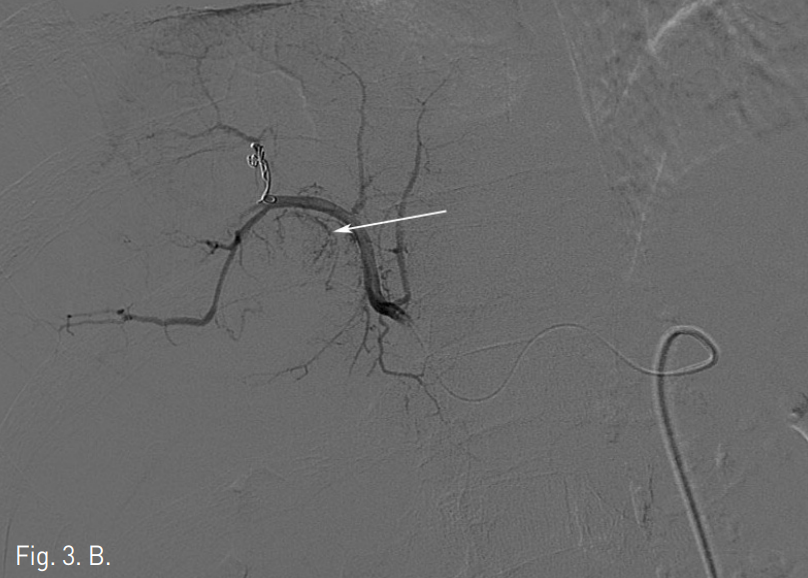

초음파 유도 하에 우측 대퇴동맥을 천자하여 5F vascular sheath를 삽입함. 5F RH catheter (Cook, Bloomington, USA)로 복강동맥을 선택한 후 시행한 동맥조영술에서 우간동맥 S7을 담당하는 분지동맥에서 기원하는 4cm 크기의 가성 동맥류가 관찰되었다(Fig. 3A). 먼저 RH catheter 내부에 2.2F microcatheter (Progreat, Terumo, Tokyo, Japan)를 삽입하여 가성 동맥류가 기원하는 혈관을 초선택하여 4개의 미세코일 (3mm x 2cm, Tornado embolization microcoil: Cook, Bloomington, IN, USA)을 이용해 색전하였다. 색전 후 시행한 동맥조영술에서 가성동맥류는 더 이상 조영되지 않았다. Coil 색전술 후 동맥조영술에서 인접하여 같은 분지동맥의 좀 더 근위부 동맥에 의해 공급받는 4.2cm 크기의 간세포암종으로 생각되는 비정상적인 과혈관성 병변이 좀 더 뚜렷하게 관찰되었다(Fig. 3B). 이후 과혈관성 병변을 공급하는 우간동맥의 분지동맥을 미세카테터로 초선택하여 항암제(Adriamycin 50mg)와 색전물질(Lipiodol 10cc)의 혼합물을 이용하여 화학색전술을 시행하였다. 화학색전 후 시행한 동맥조영술에서 종양이 조영되지 않고 내부가 lipiodol로 침착된 것 확인 후 시술을 종료하였다(Fig. 3C).

Fig. 3

A. Celiac arteriogram shows pseudoaneurysm with jet flow (arrow) from right posterior superior hepatic artery.

B. Right posterior hepatic arteriogram after coil embolization shows no extravasation with pseudoaneurysm. Hepatoma is supplied by just proximal arterial branches (arrow).

C. Fluoroscopic image after coil and chemoembolization shows dense lipiodol uptake in the right postero-superior lobe of the liver.